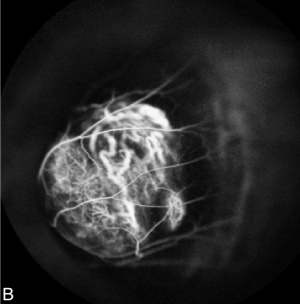

Fluorescein and indocyanine Angiography (FA + ICG-A) was performed and displayed the presence of an irregularly pigmented choroidal lesion and an hyperfluorescence with atypical circulation (Figures 4A and 4B). Optical coherence tomography showed a detachment of the neuroepithelium (Figure 5).

Figure 4B. Indocyanine Angiography showed irregular hyperfluorescence with atypical circulation